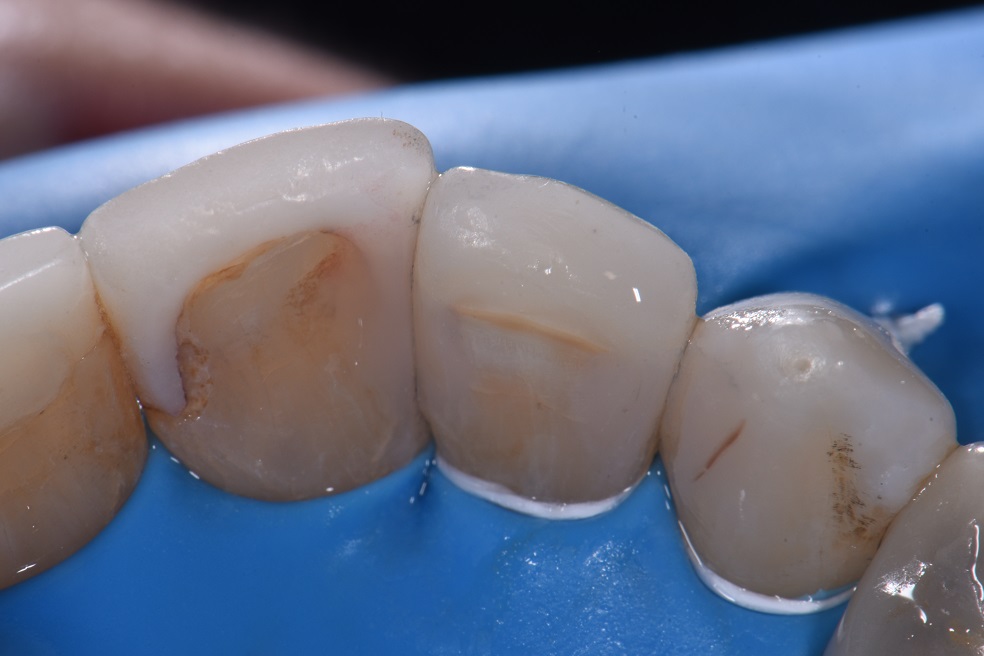

Dental Class 3 Restoration . Preparation outline is determined by the extent of the carious lesion, defects, or old restorative material. It is generally formed with. this paper aims to provide the dentist with practical guidance on the technique for direct composite restoration. dental restoration ranges in price, dependent on what type of restoration you require and which dental clinic you are visiting. in general, the tooth preparation for a class iii direct composite restoration involves (1) obtaining access to the defect (caries,. at first glance, a class iii direct composite restoration can appear to be a fairly routine procedure.